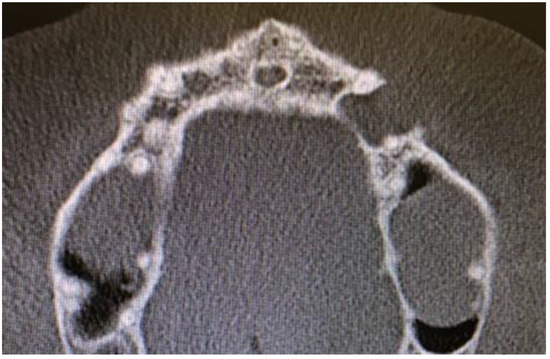

Cone beam computed tomography (CBCT) evaluation revealed the perforation of the buccal cortical bone plate, with expansion towards soft tissues, measuring about 6 mm at longest diameter (Figure 3 and Figure 4). Palatal bone plate remained without any lesions. Because of close proximity to the apex of first premolar and scheduled enucleation with bone curettage/drilling, a decision of endodontic treatment 24 was scheduled. Secondly, such treatment was also indicated because of (1) the loss of cortical plane (possible local aggressiveness of lesion), (2) possible GOC/BOC or other dental-related cyst/tumor occurrence; (3) possible teeth pulp necrosis/inflammation after extensive curettage/bone drilling used for local radicalization protocol; (4) minimizing the time needed for secondary surgery if such would be necessary in case of other pathology. On CBCT further evaluation, a slight sclerotic border close to both tooth apex/roots was visible. Teeth structure remained preserved, with only the buccal cortical bone perforation. On the floor of the left maxillary sinus, a retention mucous cyst was seen; however, due to the clinical irrelevance, only a laryngologist consultation was scheduled.

Figure 4. CBCT axial view of LPC, note 23 teeth close to apex relation with lesion.